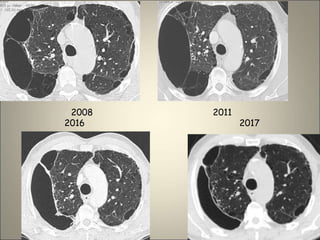

Cancérisation d’une bulle

Bulle pleine

Bulle surinfectée ou hémorragie intra bulleuse

Bulle du LSD comprimant le LM

2008 2011

2016 2017